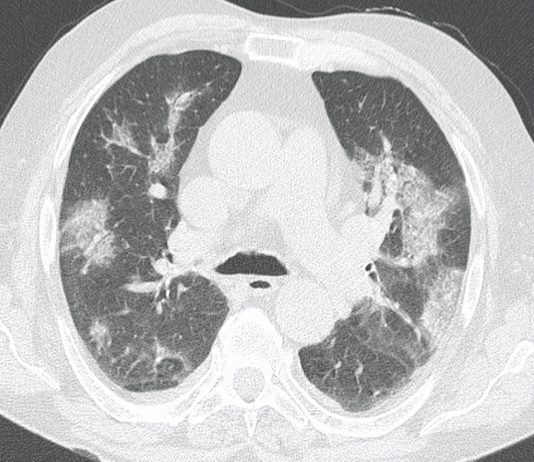

Femmina, 58 anni, asintomatica e apiretica.Esegue come paziente ambulatoriale esterna TC total body per controllo oncologico in neoplasia mammaria, sottoposta nel 2006 a mastectomia con linfoadenectomia, trattata con CT neoadiuvante e RT.